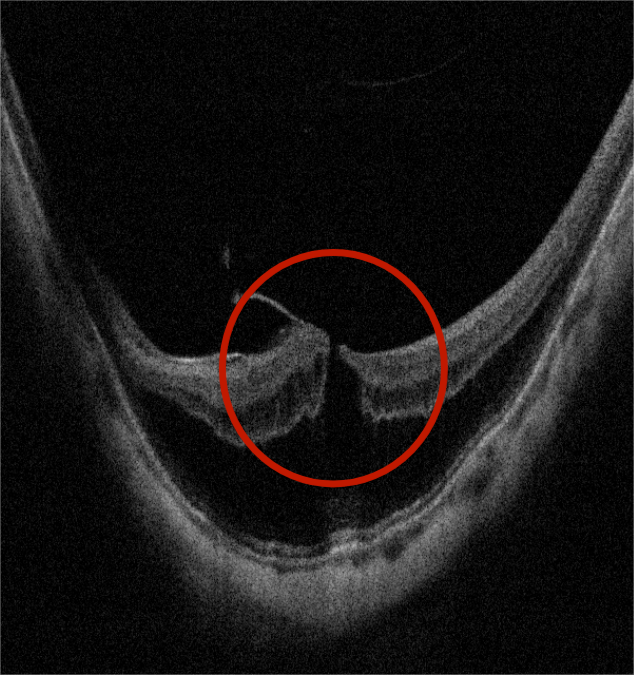

患者术前OCT,黄斑区视网膜劈裂,板层裂孔